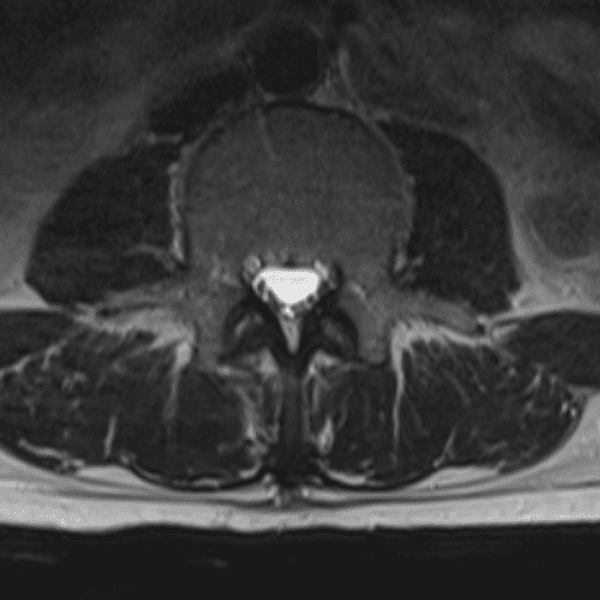

Simulates call by including subtle or difficult cases and some normals.

35 cases